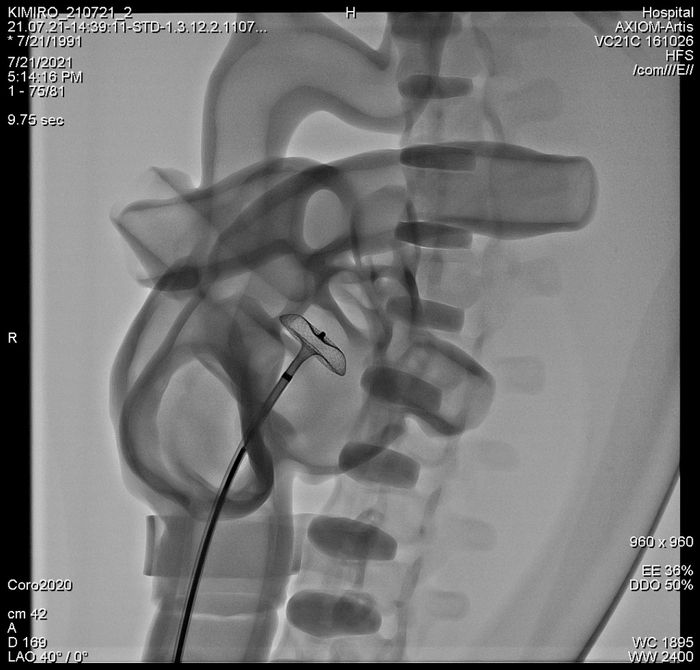

▲중재시술은 심장·심뇌혈관의 질병을 비수술적인 시술을 통해 치료하는 것으로 다양한 영상장비를 이용해 인체 내부를 관찰하면서 미세 의료기구를 체내에 삽입해 진단 또는 치료하는 기법이다. 심장·심혈관 중재시술은 매년 수술 빈도가 증가하지만 의료사고 위험성도 높아지고 있다. 2023년 기준 관련 의료진은 사실상 공백 상태로 전문 의료진 양성이 매우 시급하다.

심비스타가 개발한 중재시술 훈련 시뮬레이터는 실제 심장박동이 뛰고 혈류가 순환하고 호흡하는 가상 환자인 물리시뮬레이터와 실제 시술 현장과 동일한 환경, 확장현실(XR)을 통해 시술의 전단계를 코칭해주는 가상 엑스-레이(X-ray) 이미징 시스템이 결합됐다. 22개 대학병원에서 50여명 전문의와 4차례 사용성 평가를 수행했고 90점 이상의 점수를 획득했다.

심비스타 중재시술 훈련 시뮬레이터.